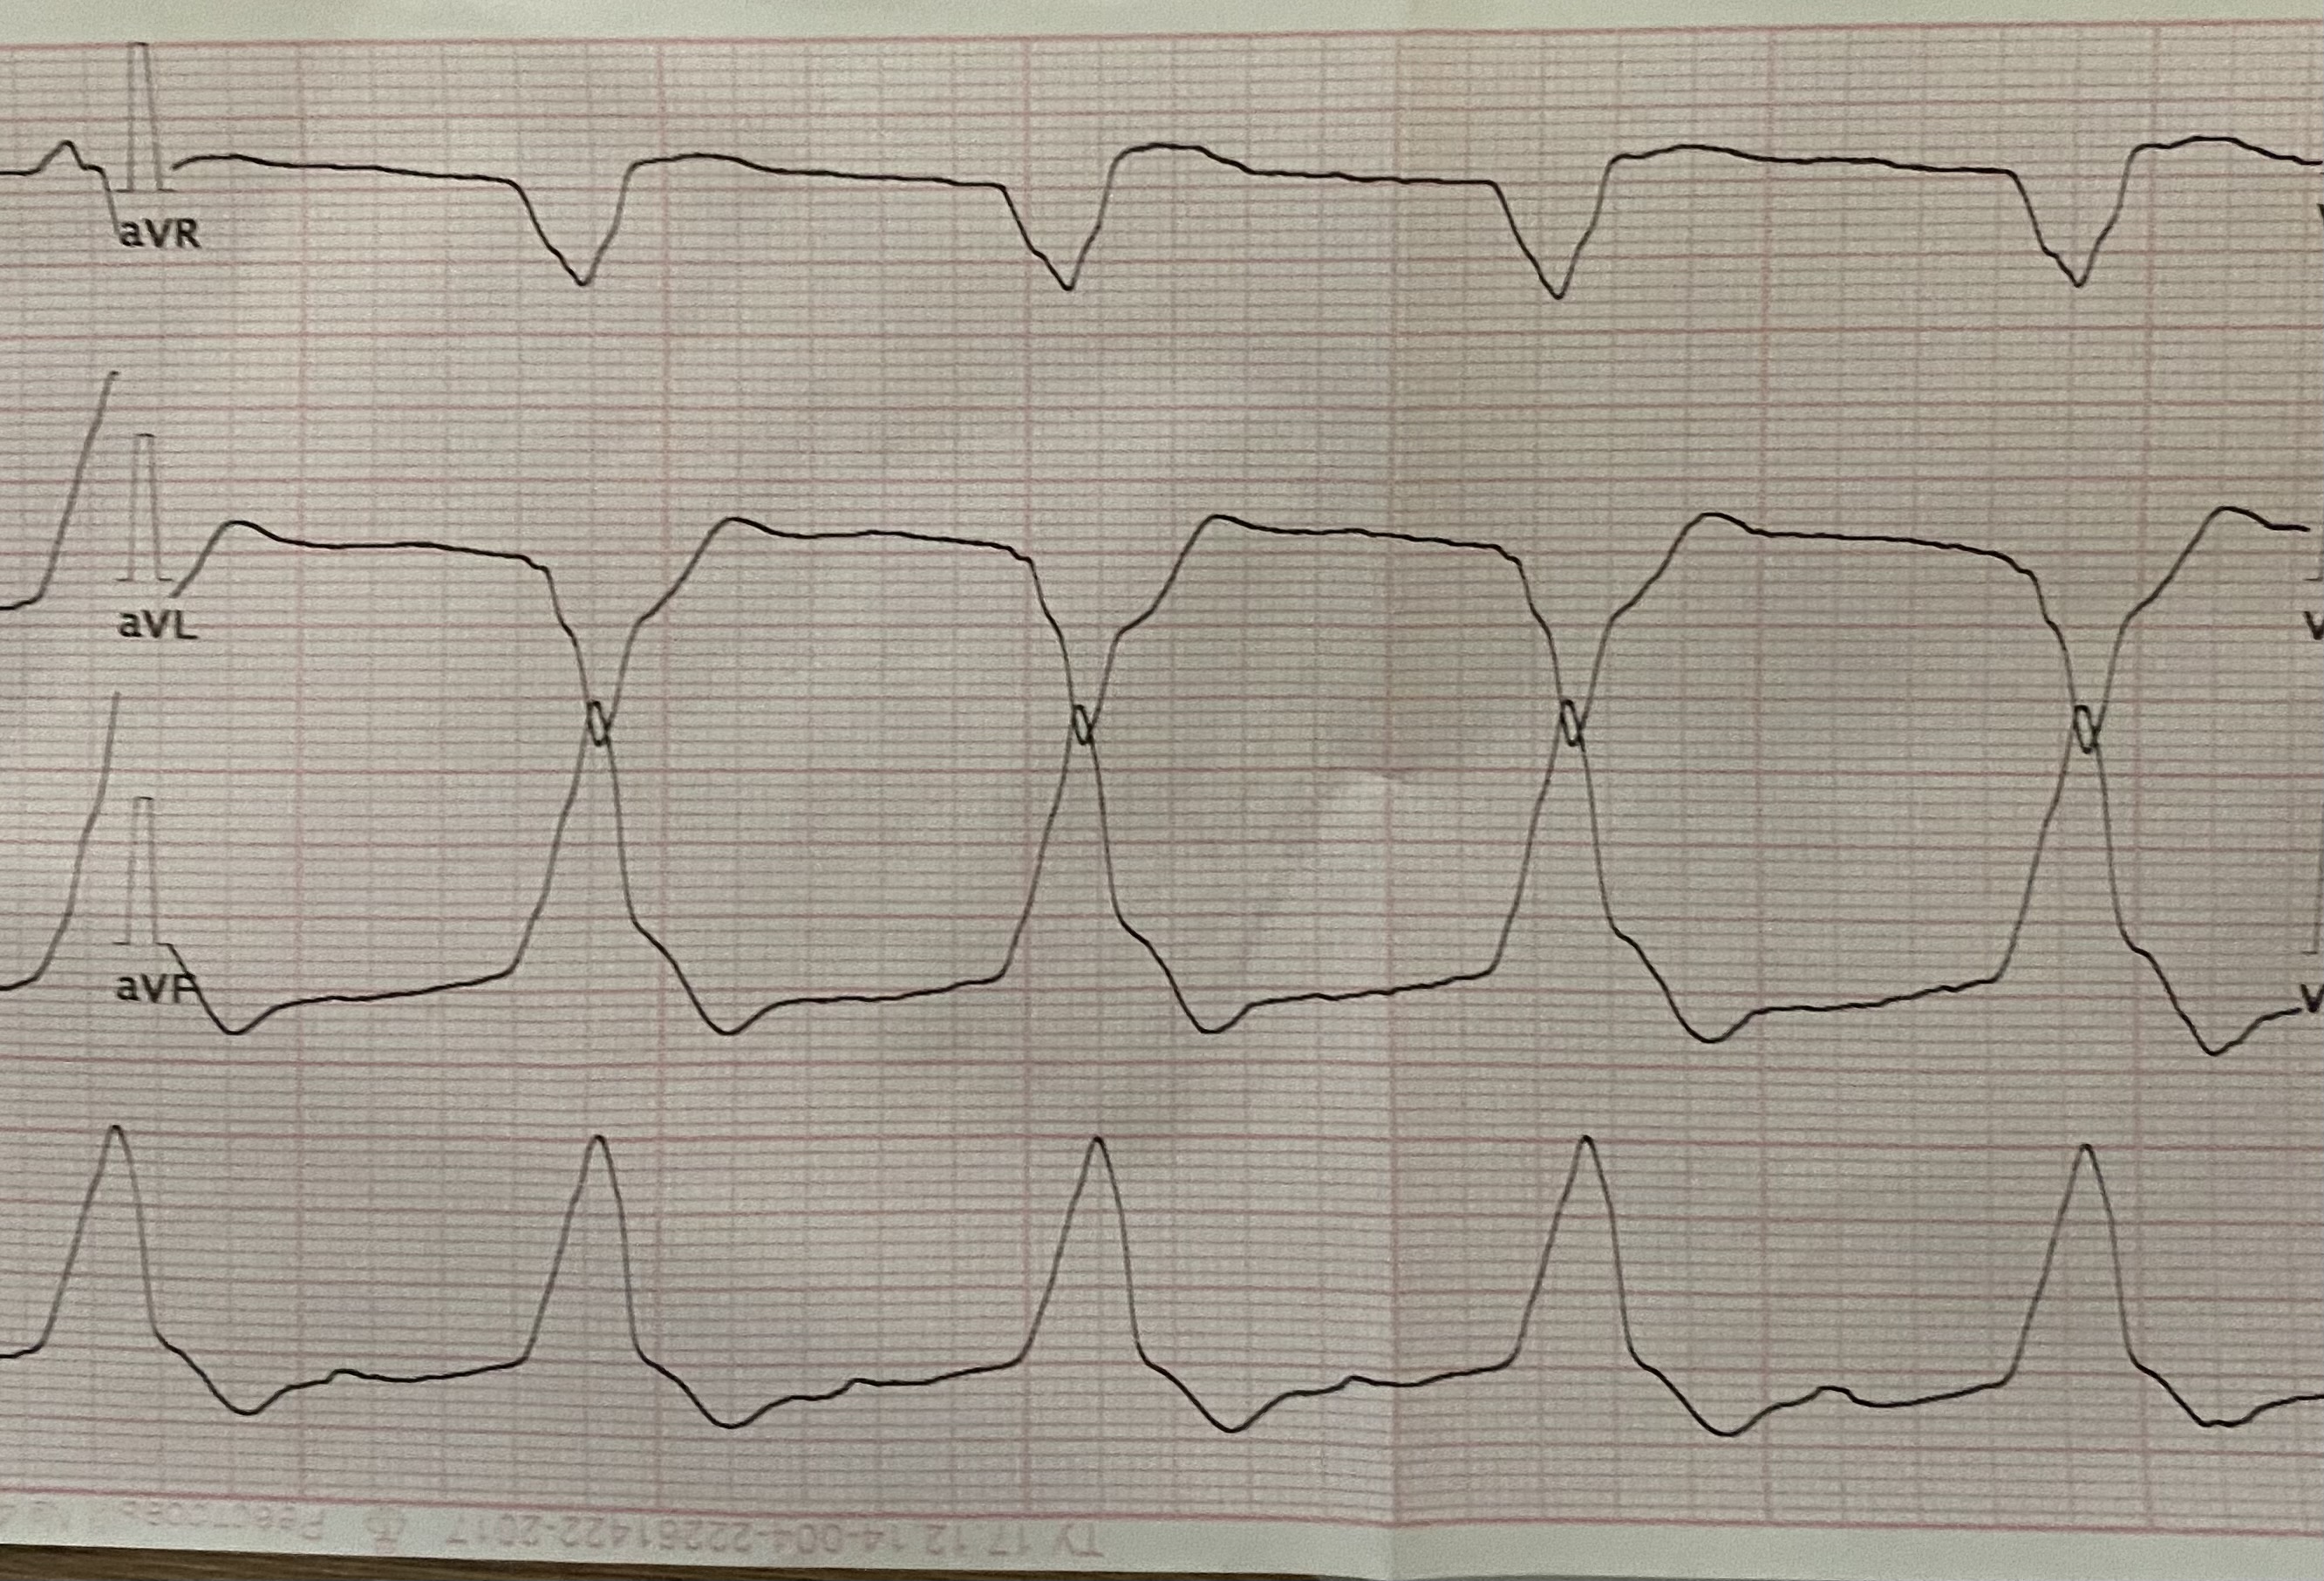

УИР

Обсуждалось здесь https://vk.com/club84409679?w=wall-84409679_13171%2Fall